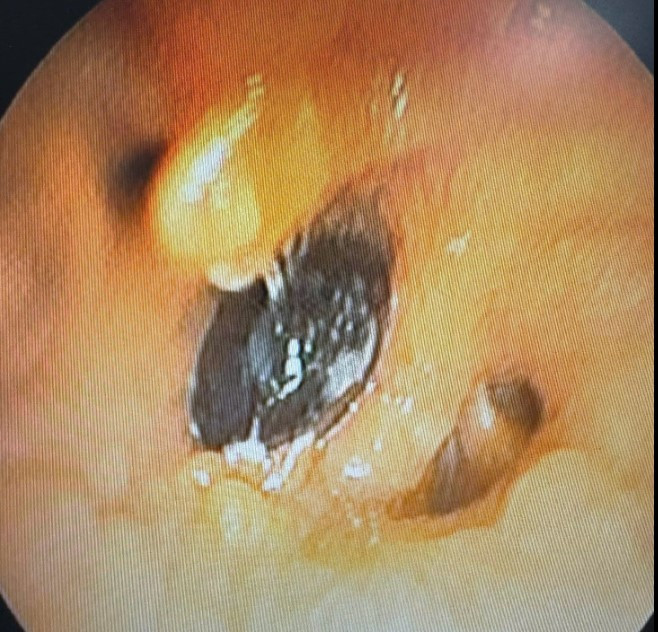

hat.jpg

Hạt hồng xiêm được lấy ra - Ảnh BVCC

Các bác sĩ Khoa Nội hô hấp – Miễn dịch dị ứng phối hợp với Khoa Phẫu thuật - Gây mê hồi sức đã tiến hành nội soi phế quản ống mềm và gắp thành công dị vật ra ngoài.

Sau can thiệp, tình trạng hô hấp của bệnh nhân cải thiện rõ rệt, giảm ho, giảm khó thở.